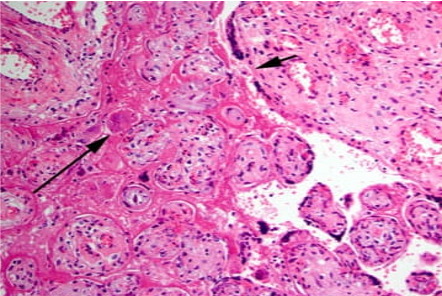

The four most common patterns of abnormal placentation/placental injury are:

4. Chronic villitis of unknown/immune etiology (non‑infectious)

Examples of abnormal immune placentation